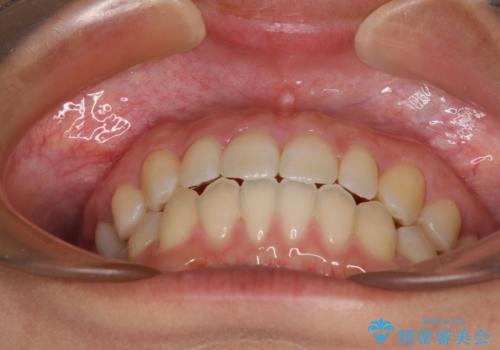

隙間だらけの歯列 インビザラインで改善

- 2年11ヶ月

空隙歯列(すきっ歯)は、舌の突出癖をある程度改善できたとしても、後戻りにより隙間が開きやすいと言われています。

裏側から細いワイヤーで保定するとともに、睡眠時のマウスピース装着を徹底していただくことで、後戻りを最小限にとどめます。